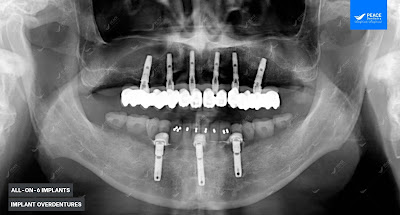

Đây là ca lâm sàng mà bác sĩ cấy ghép implant tại Peace Dentistry (https://nhakhoapeace.com/) đã áp dụng 2 kỹ thuật hiện đại: All-on-6 Implants & Hàm phủ trên Implant - Implant overdentures.

Do mất răng nhiều năm nên cả 2 hàm đều đã tiêu xương khá nhiều nhưng hàm trên vẫn đủ xương để thực hiện giải pháp All-on-6 Implants (Implant toàn hàm). Với hàm dưới tiêu xương nghiêm trọng hơn: vùng răng hàm nhai không đủ khối lượng xương để cấy ghép Implant, nhưng xương hàm vùng răng cửa vẫn tương đối tốt và đủ khối lượng xương để cấy ghép Implant.

- Hàm trên: All on 6 Implants với 6 trụ Implant Dentium Super Line (made in USA), cố định hàm BioHPP. Phục hình tức thì;

- Hàm dưới: Hàm phủ trên Implant (Implant overdentures) với 3 trụ Implant được cấy ghép vào xương hàm tại các vùng răng có xương dày và tốt nhất, kết hợp sử dụng hàm Composite trên 3 Implant này;

Lưu ý: hàm phủ trên Implant là giải pháp tối ưu trong trường hợp này: vừa phù hợp với tình trạng xương hàm, vừa tiết kiệm chi phí mà vẫn mang lại hiệu quả cao: Hàm Composite trên 3 Implant giúp tăng sức nhai vượt trội và tăng tính lưu giữ.